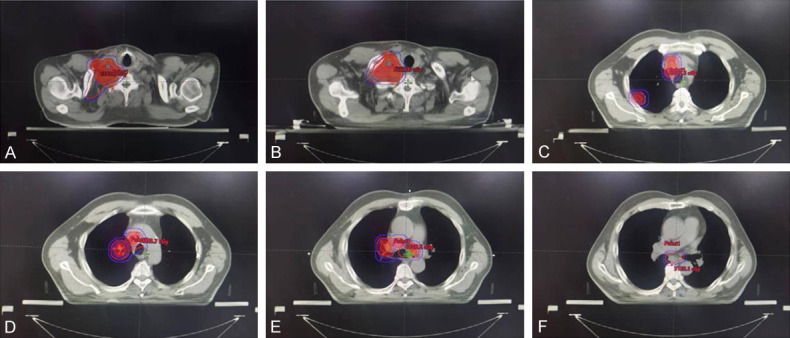

On October 23, 2020 and November 13, 2020, the patient was administrated with 2 cycle of PC regimen chemotherapy (Pemetrexed 500 mg/m2 and Carboplatin AUC = 5) with the consent from the patient. After the 2-month follow-up, the lesions achieved disease progression (PD) by Response Evaluation Criteria In Solid Tumors (RECIST) (version 1.1). Maximum diameter of cervical lymph nodes enlarged from 3.7 cm to 4.6 cm (Figure 2). On Dec 5, 2020, the patient was administrated with the first cycle of TP regimen chemotherapy (Albumin paclitaxel 260 mg/m2 day 1 and Cisplatin 75 mg/m2 day 1). Shortly, the patient received elective node irradiation (ENI) from Dec 21, 2020 to Feb 12, 2021 (Figure 3). Intensity modulated radiotherapy (IMRT) was adopted as the technique. Gross target volume (GTV) included the primary tumor located in the upper lobe of right lung, the metastatic tumor at the same lobe, and all the lymph nodes in the cervical and mediastinal region. The clinical target volume (CTV) covered all the GTV and the lymph node regions with observable metastatic lymph nodes, including supraclavicular, 2R, 4R, 4L, and subcarinal regions. The planning target volume (PTV) was defined as the CTV plus 0.5 cm margins (Figure 3). The total dose of PTV was 4785 cGy/29 f, and the dose of GTV was up to 5800 cGy/29 f using simultaneous integrated boost (SIB) technique. Dose constraints for normal tissues were required as follows: maximum dose for spinal cord should be less than 45 Gy; the mean lung dose was less than 12 Gy, and less than 25% of the lung volume received 20 Gy (V20<25%); and the mean cardiac dose was less than 30 Gy, with V30<40% and V40<30%. Sequentially, the patient received the second to the sixth cycles of TP regimen chemotherapy from Feb 18, 2021 to June 14, 2021. The assessment on July 1, 2021 was partial response (PR) after sCRT.

Figure 3.

Target volume of radiotherapy. Inner dark red regions represented GTV. Outer red region represented CTV, and blue lines contoured the PTV for both GTV and CTV, respectively. A, B. Target volume at supraclavicular region. C. Target volume at thoracic inlet. GTV included mediastinal lymph nodes and metastatic tumor at the peripheral region of upper right lobe. D. Target volume at the level of aortic arch. E. Target volume at the level of tracheal carina. F. Target volume at subcarinal region. Gross target volume (GTV); clinical target volume (CTV); planning target volume (PTV).